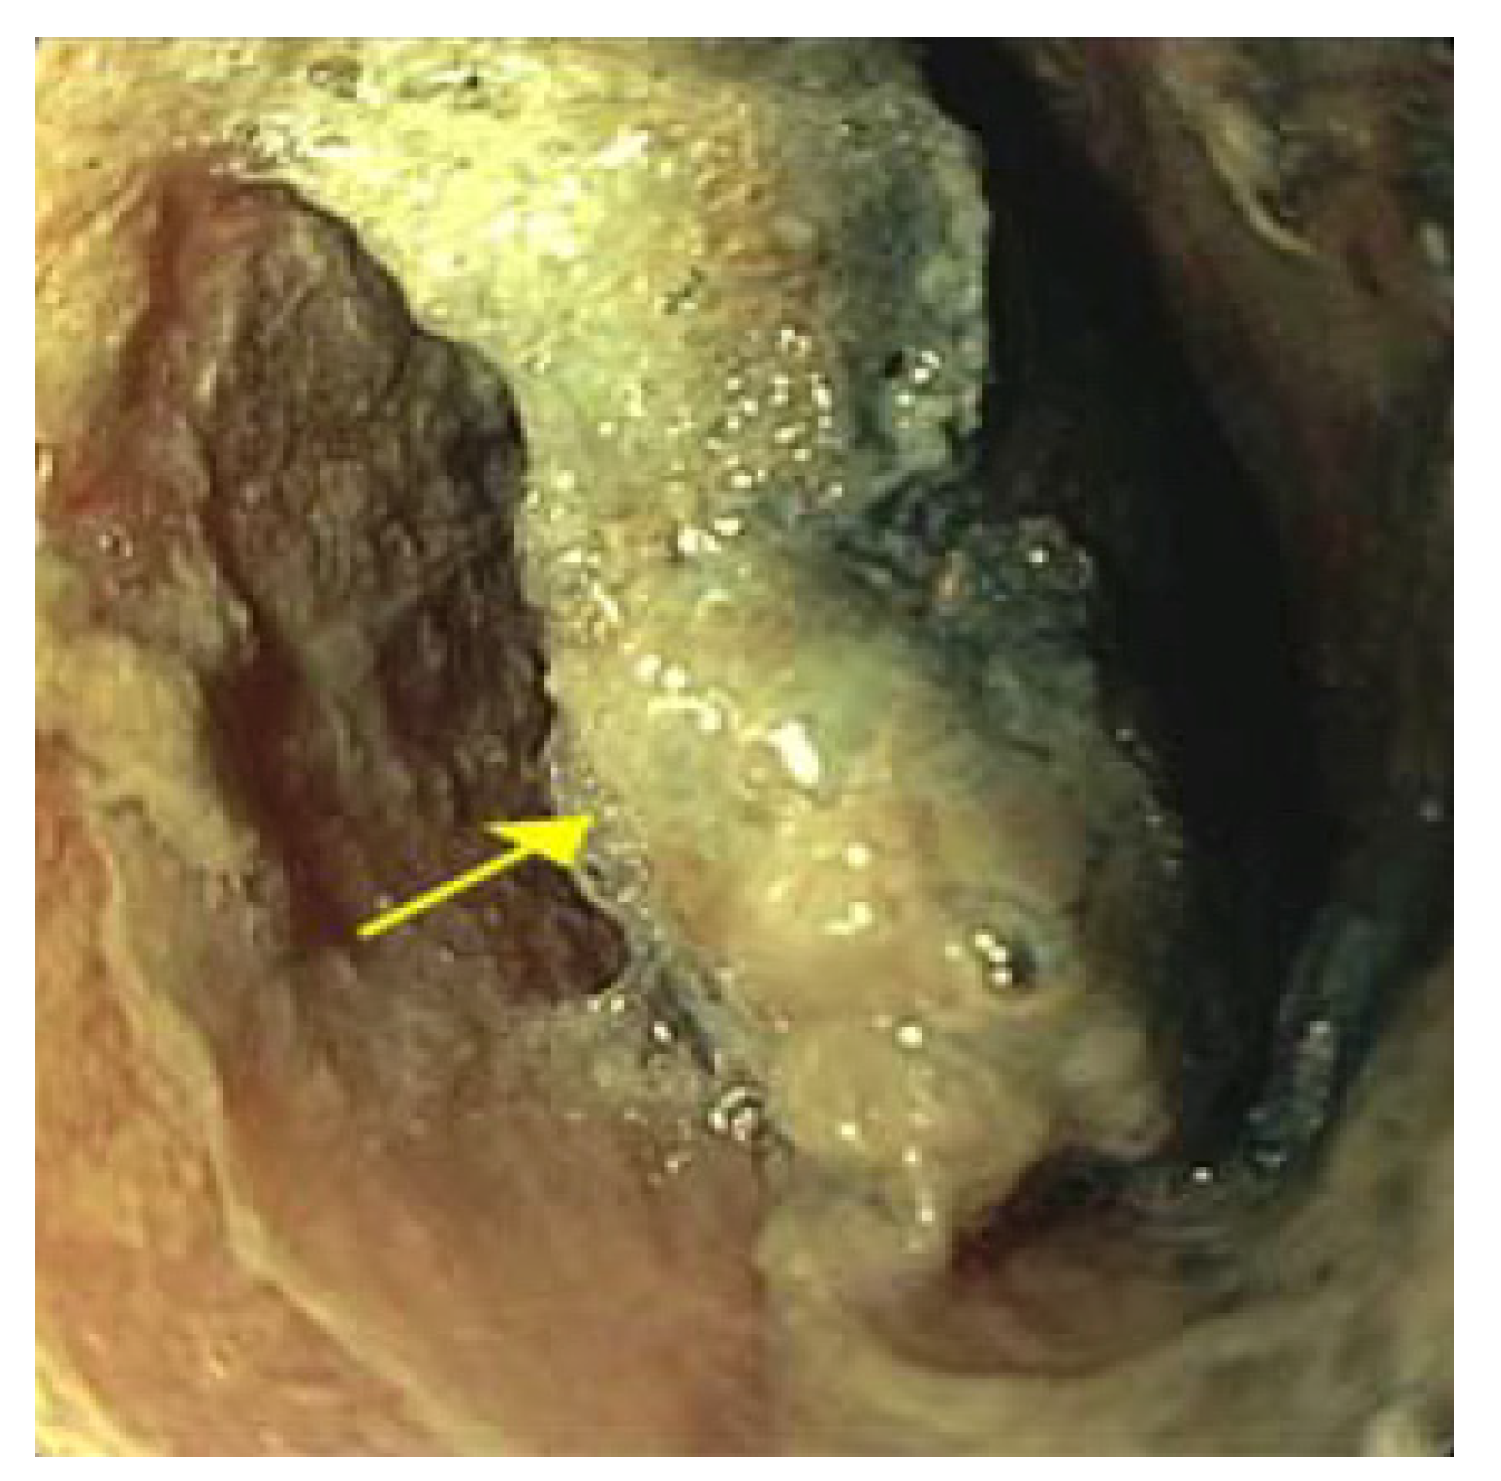

2. Case Presentation